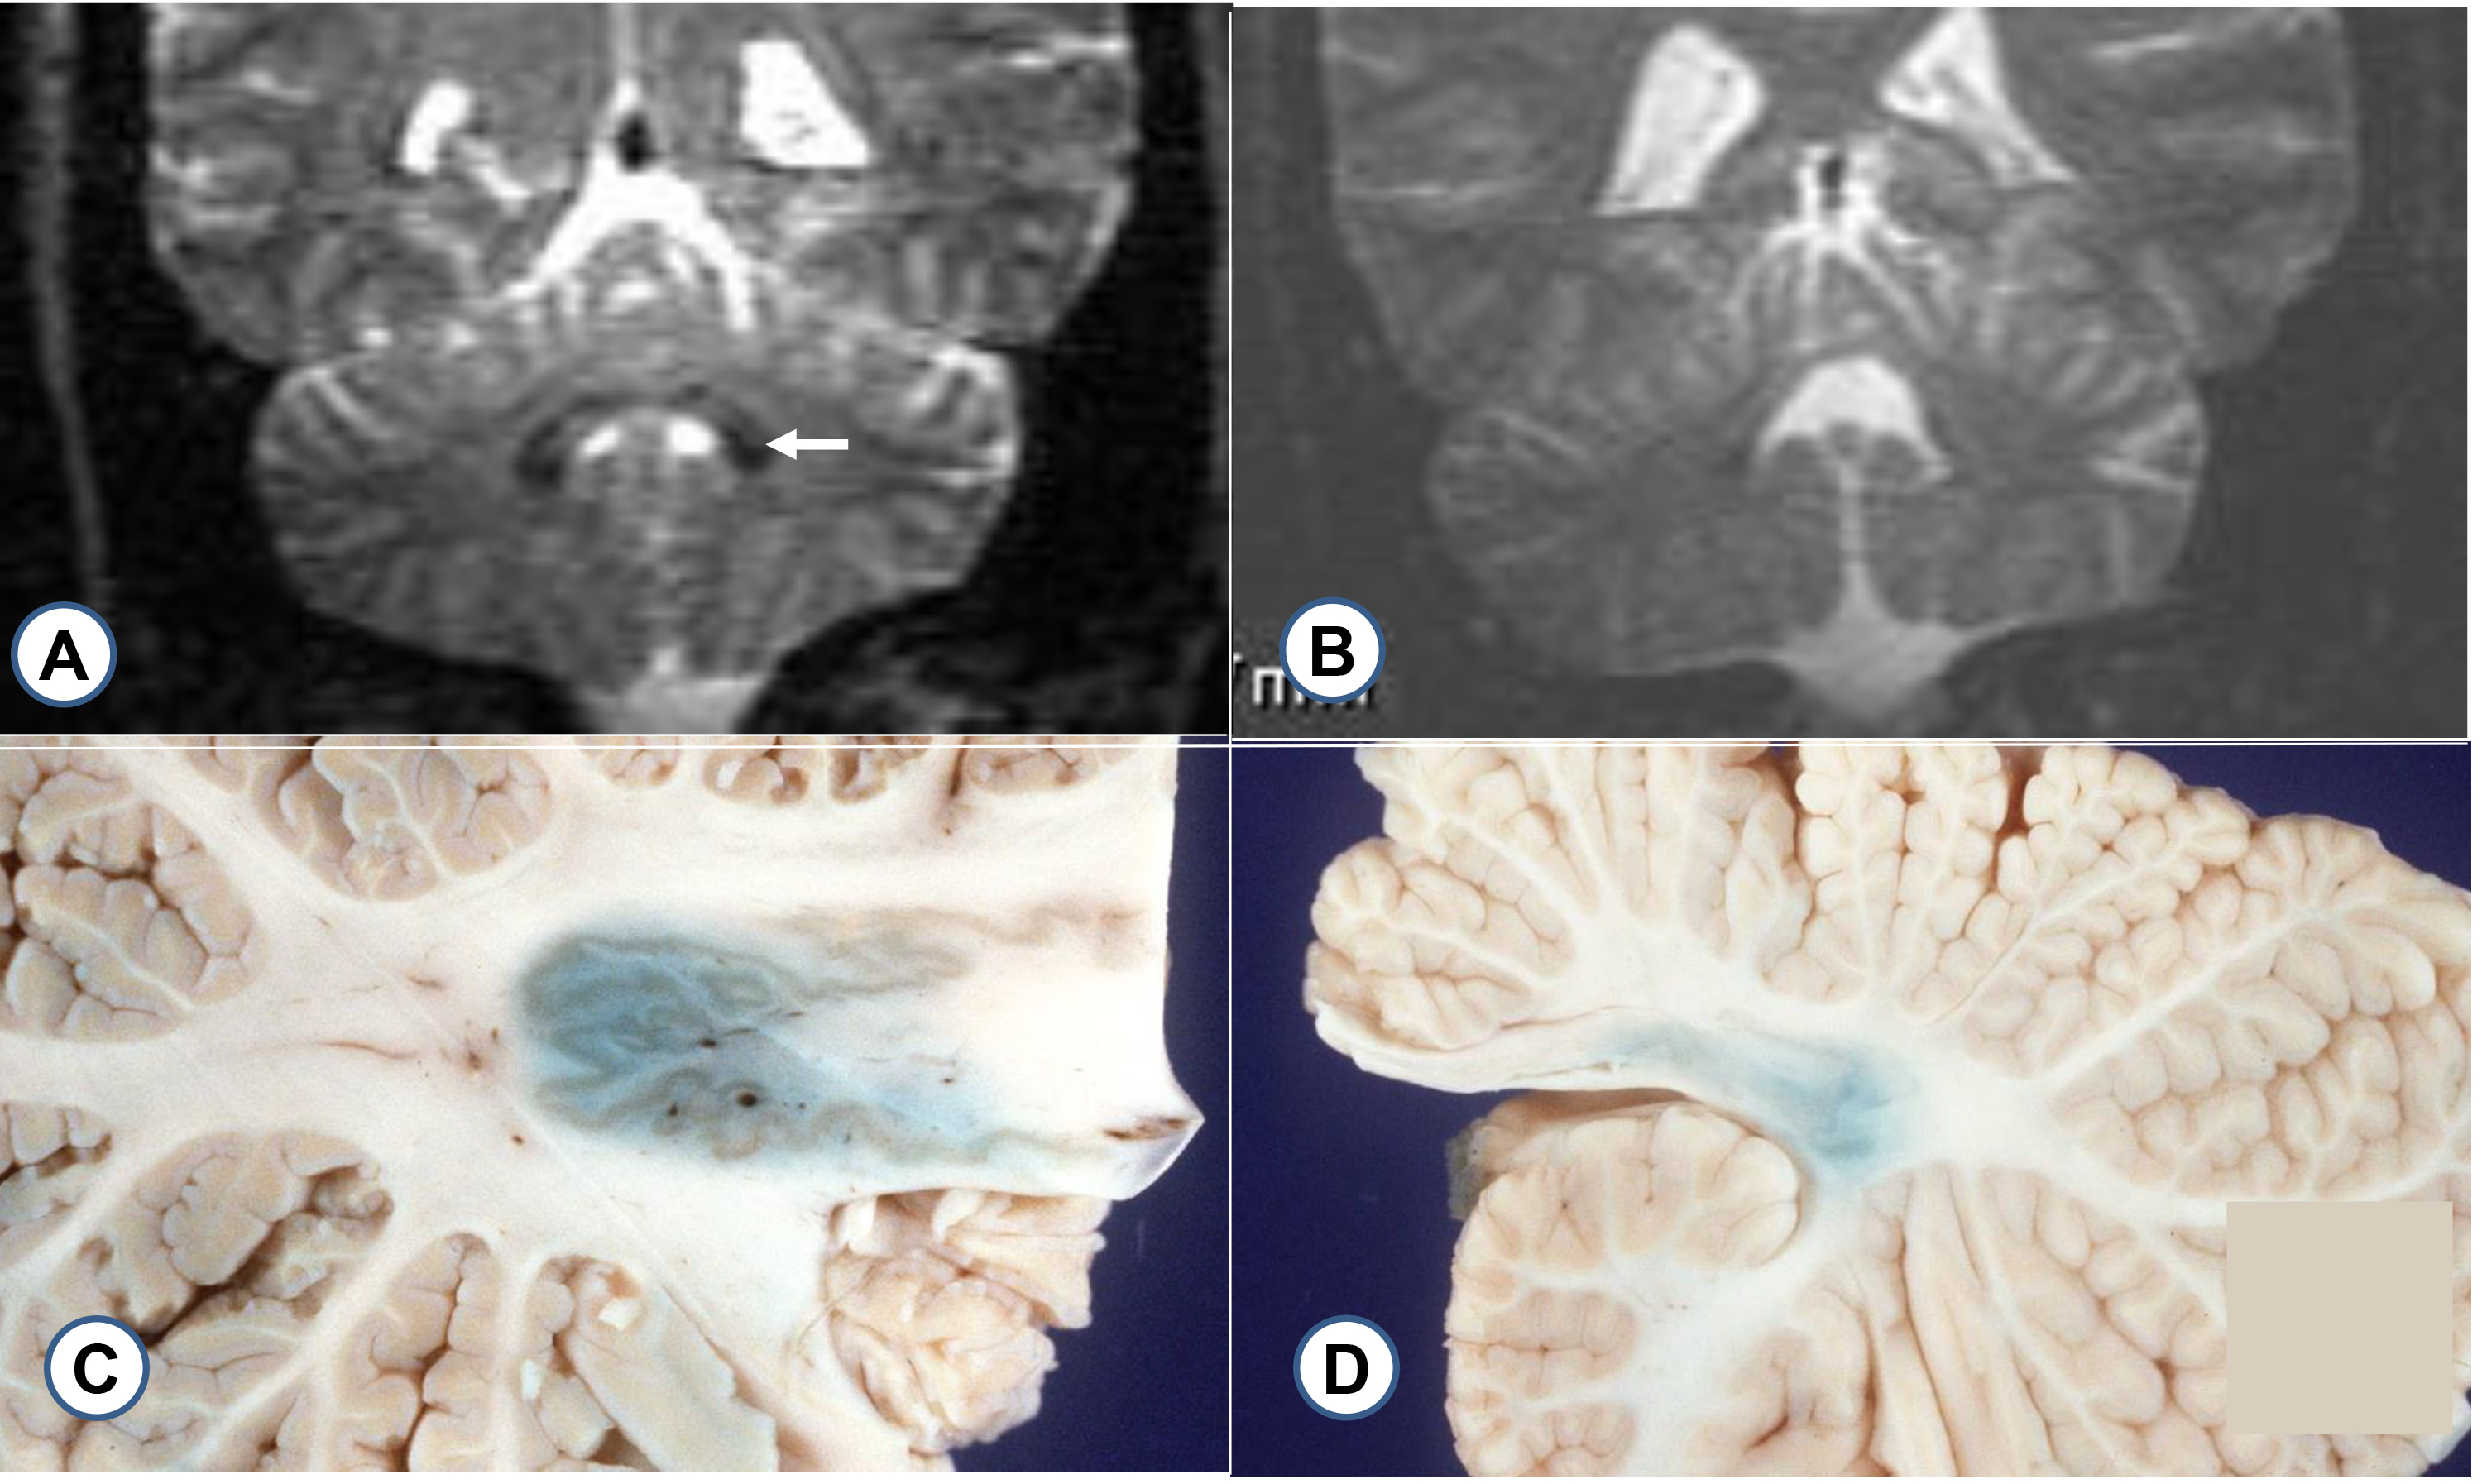

The dentate nucleus is naturally rich in iron, and, based on the paramagnetic

effect of the metal, T2-weighted magnetic resonance images show the nucleus in

the cerebellum to advantage (Fig. 6C,D). Contrary to Waldvogel et al.

[4] and Boddaert, et al. [5], however, the author asserts that

Friedreich ataxia causes shrinkage of the dentate nucleus and reduced

paramagnetic iron effect (Fig. 6). Fig. 6 shows macroscopic iron stains of the

dentate nucleus in FA (Fig. 6B) and a control specimen (Fig. 6A). Perls’s [8]iron stain generates a crisp outline of the normal meandering gray matter ribbon

(Fig. 6A) while the blue reaction product in FA is consistent with a globular

collapse of the dentate nucleus (Fig. 6D). The macroscopic iron stain is

misleading as systematic chemical assay of iron in digests of 9 dentate nuclei

and 9 control specimens showed no difference in the levels of the metal [9].

Fig. 6.Magnetic resonance images of the dentate nucleus in FA and a control; macrostain of iron in formalin-fixed cerebellum. (A) T2 weighted image of a control dentate nucleus (arrow); (B) FA; (C) macrostain for iron in a normal dentate nucleus; (D) FA. (A) The arrow shows the outline of the iron-rich normal dentate nucleus; (B) In FA, the paramagnetic effect of iron in the dentate nucleus has become indistinct. (C) and (D) Slices of cerebellum were overlaid with Perls’s [8] reagents. The normal specimen (A) shows the outline of the gray matter ribbon and a more diffuse reaction product. In FA (B), only some diffuse reaction product remains. The gray matter of the dentate nucleus is no longer distinct.